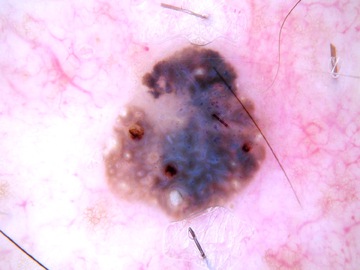

Case: 287